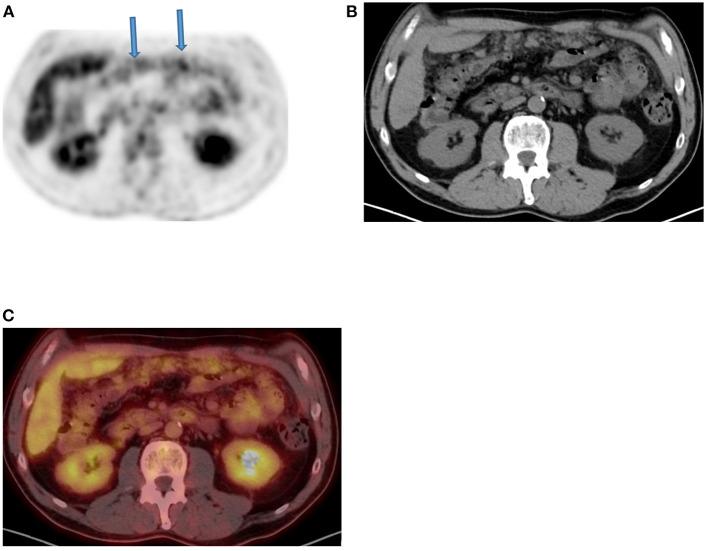

Since its introduction into clinical practice, multimodality imaging has revolutionized diagnostic imaging for both oncologic and non-oncologic pathologies. F-fluorodeoxyglucose (F-FDG) PET/CT imaging which takes advantage of increased anaerobic glycolysis that occurs in tumor cells (Warburg effect) has gained significant clinical relevance in the management of most, if not all oncologic conditions. Because FDG is taken by both normal and abnormal tissues, PET/CT imaging may demonstrate several normal variants and imaging pitfalls. These may ultimately impact disease detection and diagnostic accuracy. Imaging specialists (nuclear medicine physicians and radiologists) must demonstrate a thorough understanding of normal and physiologic variants in the distribution of F-FDG; including potential imaging pitfalls and technical artifacts to minimize misinterpretation of images. The normal physiologic course of F-FDG results in a variable degree of uptake in the stomach, liver, spleen, small and large bowel. Urinary excretion results in renal, ureteric, and urinary bladder uptake. Technical artifacts can occur due to motion, truncation as well as the effects of contrast agents and metallic hardware. Using pictorial illustrations, this paper aims to describe the variants of physiologic F-FDG uptake that may mimic pathology as well as potential benign conditions that may result in misinterpretation of PET/CT images in common oncologic conditions of the abdomen and pelvis.

自从多模态成像技术引入临床实践以来,它已经彻底改变了肿瘤和非肿瘤疾病的诊断成像。利用肿瘤细胞中发生的无氧糖酵解增加(瓦伯格效应)的F-氟脱氧葡萄糖(F-FDG)PET/CT成像,在大多数(即使不是全部)肿瘤疾病的管理中已具有重要的临床意义。由于正常组织和异常组织都会摄取FDG,PET/CT成像可能会显示出几种正常变异和成像陷阱。这些最终可能会影响疾病检测和诊断准确性。成像专家(核医学医师和放射科医生)必须充分了解F-FDG分布中的正常和生理变异;包括潜在的成像陷阱和技术伪影,以尽量减少对图像的错误解读。F-FDG的正常生理过程会导致胃、肝脏、脾脏、小肠和大肠出现不同程度的摄取。尿液排泄会导致肾脏、输尿管和膀胱摄取。由于运动、截断以及造影剂和金属硬件的影响,可能会出现技术伪影。本文旨在通过图片说明,描述可能模仿病变的生理性F-FDG摄取变异,以及在腹部和骨盆常见肿瘤疾病中可能导致PET/CT图像误判的潜在良性情况。